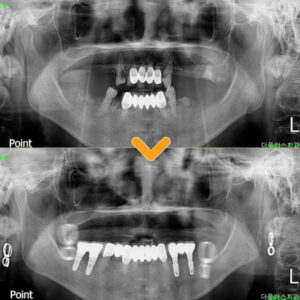

수암동치과 전체임플란트 다수의 치아를 상실했을 때 알아보아야 할 사항은?

수암동치과 전체임플란트 다수의 치아를 상실했을 때 알아보아야 할 사항은?     안녕하세요.   모든 진료에 진심을 다하는 곳, 더플러스치과입니다. ​ 임플란트는 한 번 식립되면 반영구적으로 사용되므로 처음 진행할 때는 신중함이 필요하며, 올바른 식립부터 사후 관리까지 신뢰할 수 있는 치과를 찾아 더보기…